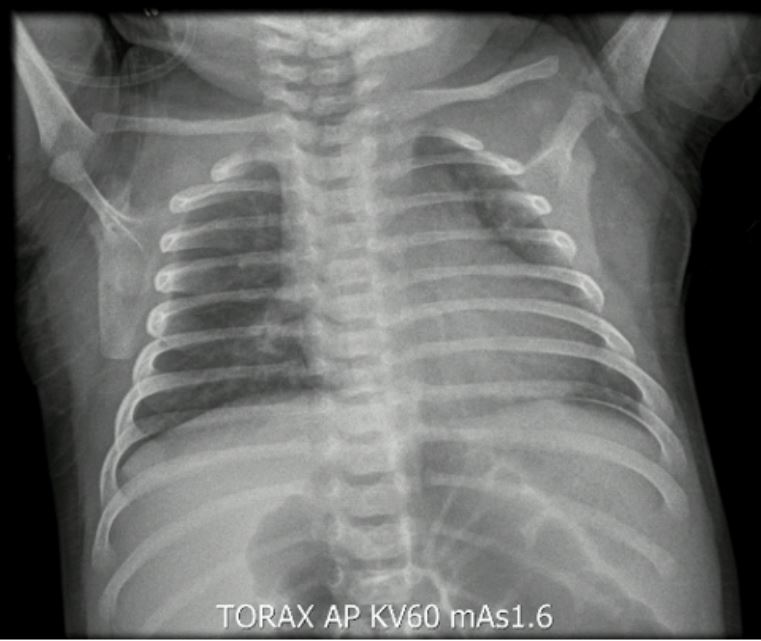

En el reingreso presentó signos de dificultad respiratoria, dados por aleteo nasal, retracciones intercostales y subcostales, hipoxemia y sibilancias a la auscultación pulmonar. La impresión diagnóstica fue de bronquiolitis (escala de Woods-Down-Ferrés = 4 puntos). Se inició oxígeno por cánula nasal y se hicieron lavados nasales. Se solicitaron exámenes paraclínicos de extensión: el panel viral de ingreso fue negativo, la radiografía de tórax mostró opacidades intersticiales de predominio parahiliar (figuras 1 y 2) y fueron negativos los hisopados rectales.